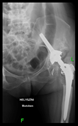

The guiding wire was inserted and controlled with fluoroscopy flashes (Figure 4). The drilling and reaming were carried out in accordance with the recommendations:

Figure 4.

The biocompatible aiming device after insertion of the guiding wire.

In all the cases operated with the above-described targeting procedure, the stems of the cups remained between the cortical bone surfaces without perforation of the linea terminalis, as shown by postoperative radiographs. There were no complicated surgical situations. In 16 cases, the wound healings were uneventful, and the hips were able to bear weight again after postoperative rehabilitation.